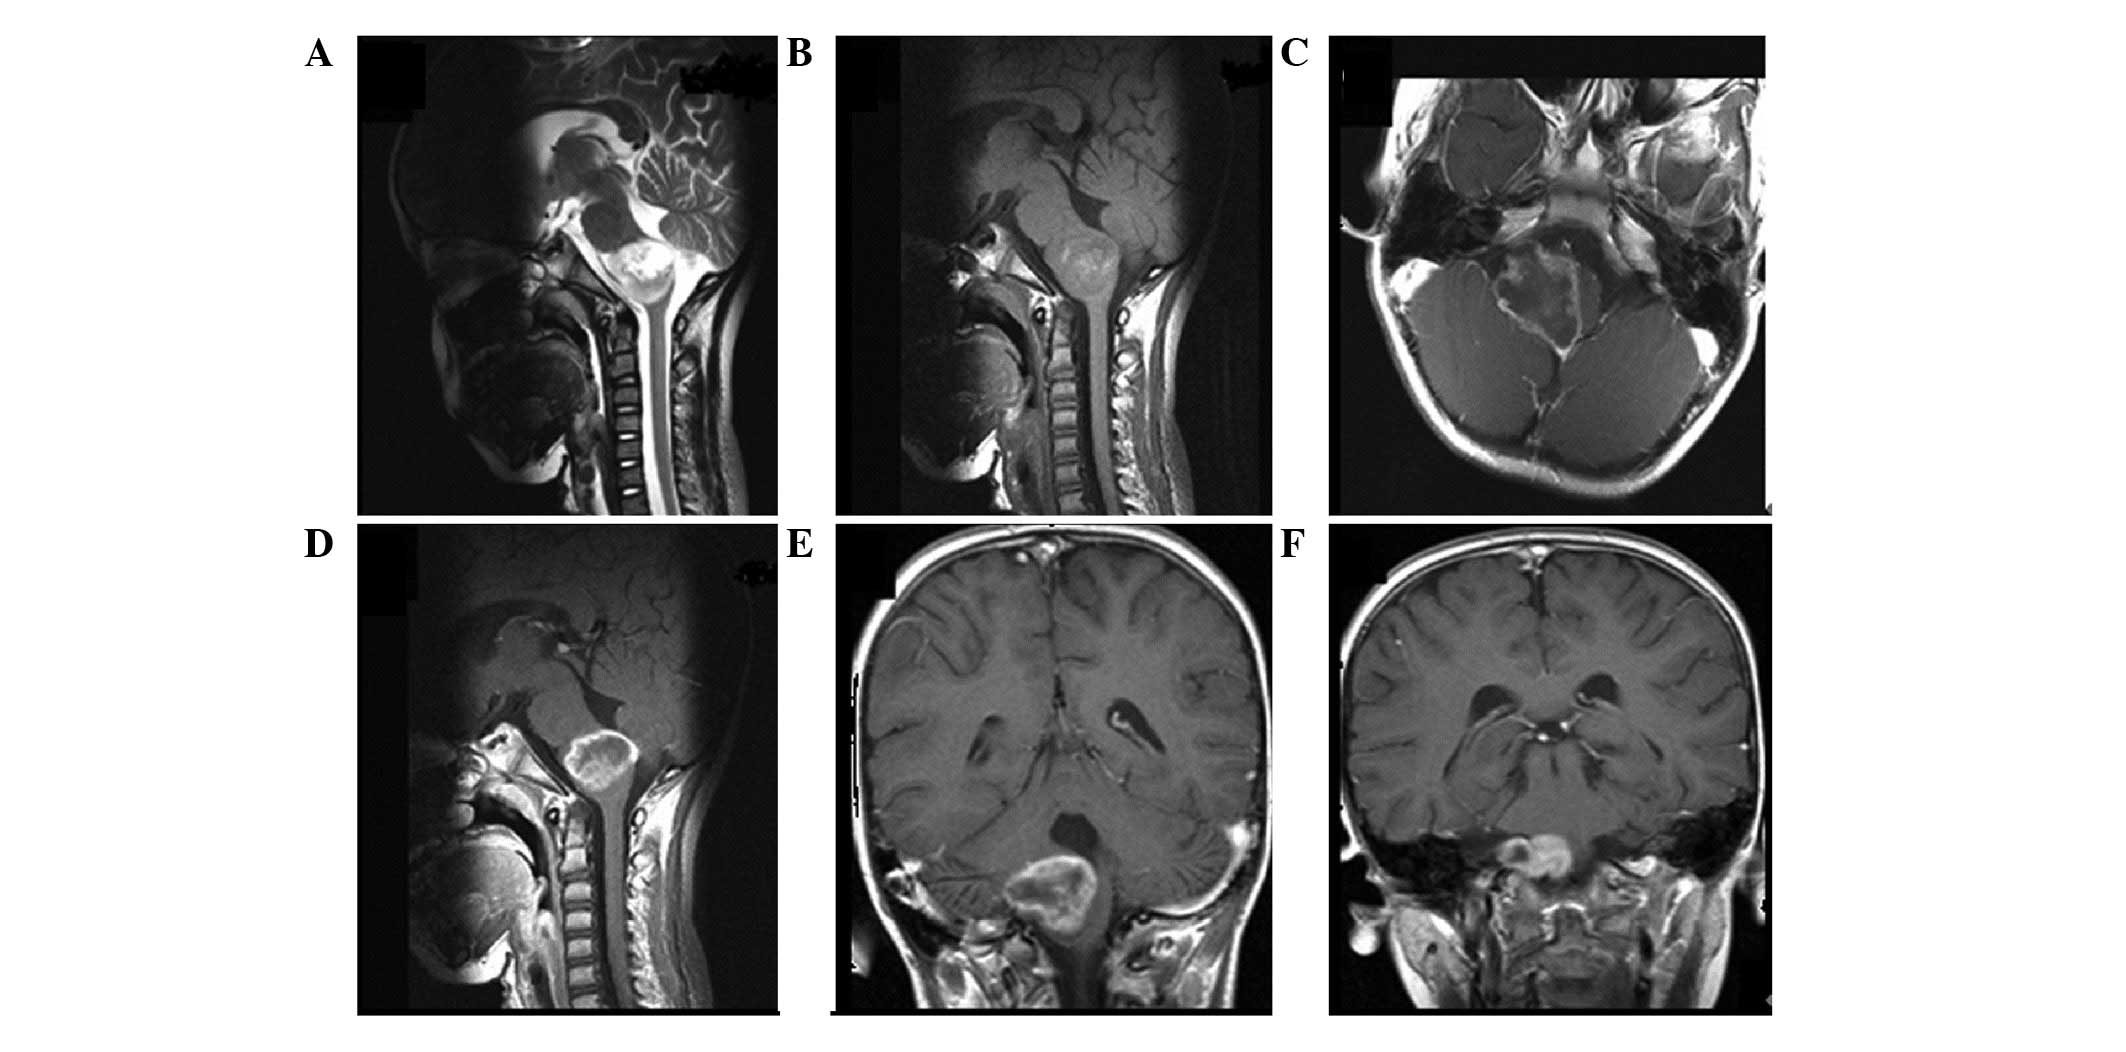

Figure 1

Patient with histological World Health Organization grade II diffuse astrocytoma and isocitrate dehydrogenase 1 mutation. Magnetic resonance imaging (A) T2-weighted, (B) T1-weighted, (C) FLAIR and (D) postcontrast T1-weighted axial as well as postcontrast T1-weighted (E) sagittal and (F) coronal (indicated by the black arrow) images demonstrated a lesion located in the posterior part of the superior frontal gyrus (non-functional region). The lesion (hyperintense on T2 images, hypointense on T1 images and hyperintense on FLAIR images with no postcontrast enhancement) showed well-demarcated, homogeneous high-signal intensity predominantly involving the white matter. No significant edema or mass effect were found adjacent to the cerebral falx. FLAIR, fluid-attenuated inversion recovery.